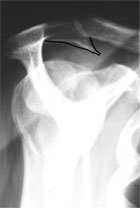

Röntgen:

Die bildgebende Diagnostik umfasst neben Röntgenaufnahmen der

Schulter in 3 Ebenen, die Aufschluss über die knöcherne

Darstellung der Schulter ergeben, die Sonographie und die Durchführung

einer Kernspintomographie der Schulter, um neben der Rupturgröße

die Qualität der Muskulatur beurteilen zu können.

Abbildung:

MRT einer Rotatorenmanschettenruptur |